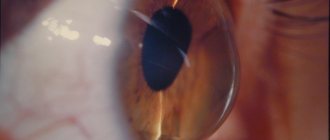

Воспаление роговицы (то есть передней прозрачной части глаза, покрывающей радужную оболочку и зрачок) называют кератитом. Одной из распространенных разновидностей заболевания является инфекционный кератит, данное воспаление может быть бактериальным, вирусным,грибковым или протозойным. Лечение инфекционного кератита определяется причиной воспаления.

Первым признаком герпетического кератита является появление небольших пузырьков на роговицы. Со временем они лопаются, на их месте образуются язвочки. Зрение ухудшается. Если поражен один глаз, то только на нем. Если вовлечены оба органа, то с обеих сторон.